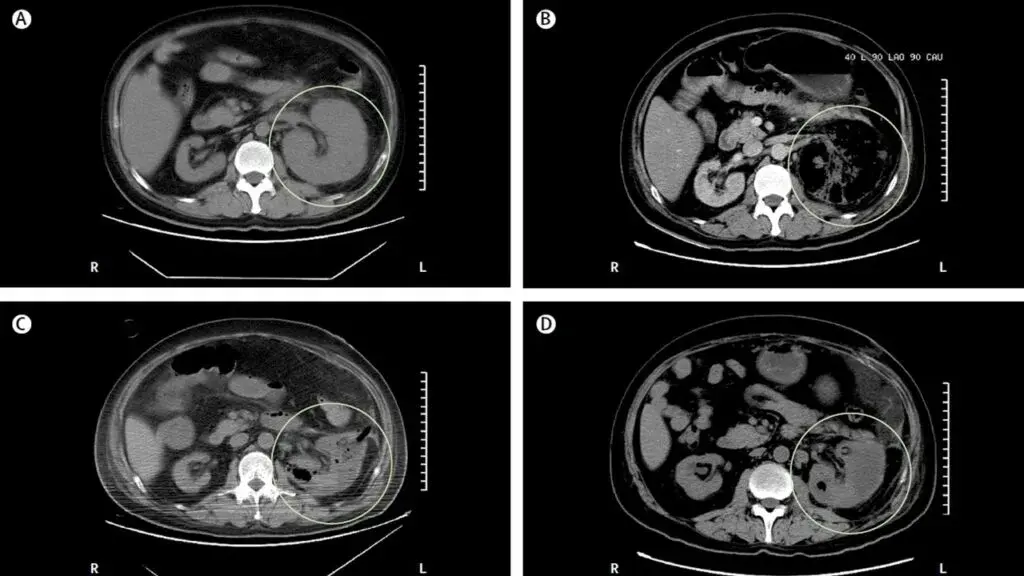

Mudança dinâmica do tamanho renal?